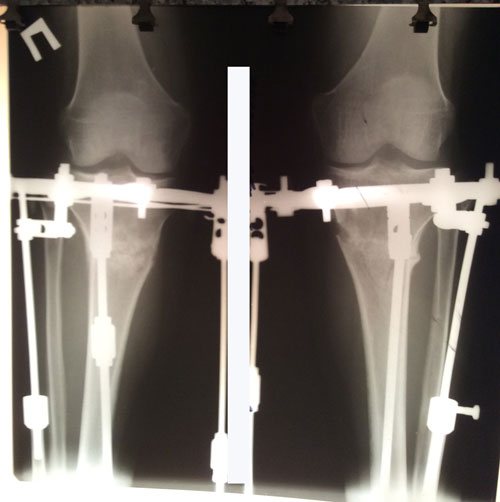

РЕНТГЕН ДО ОПЕРАЦИИ